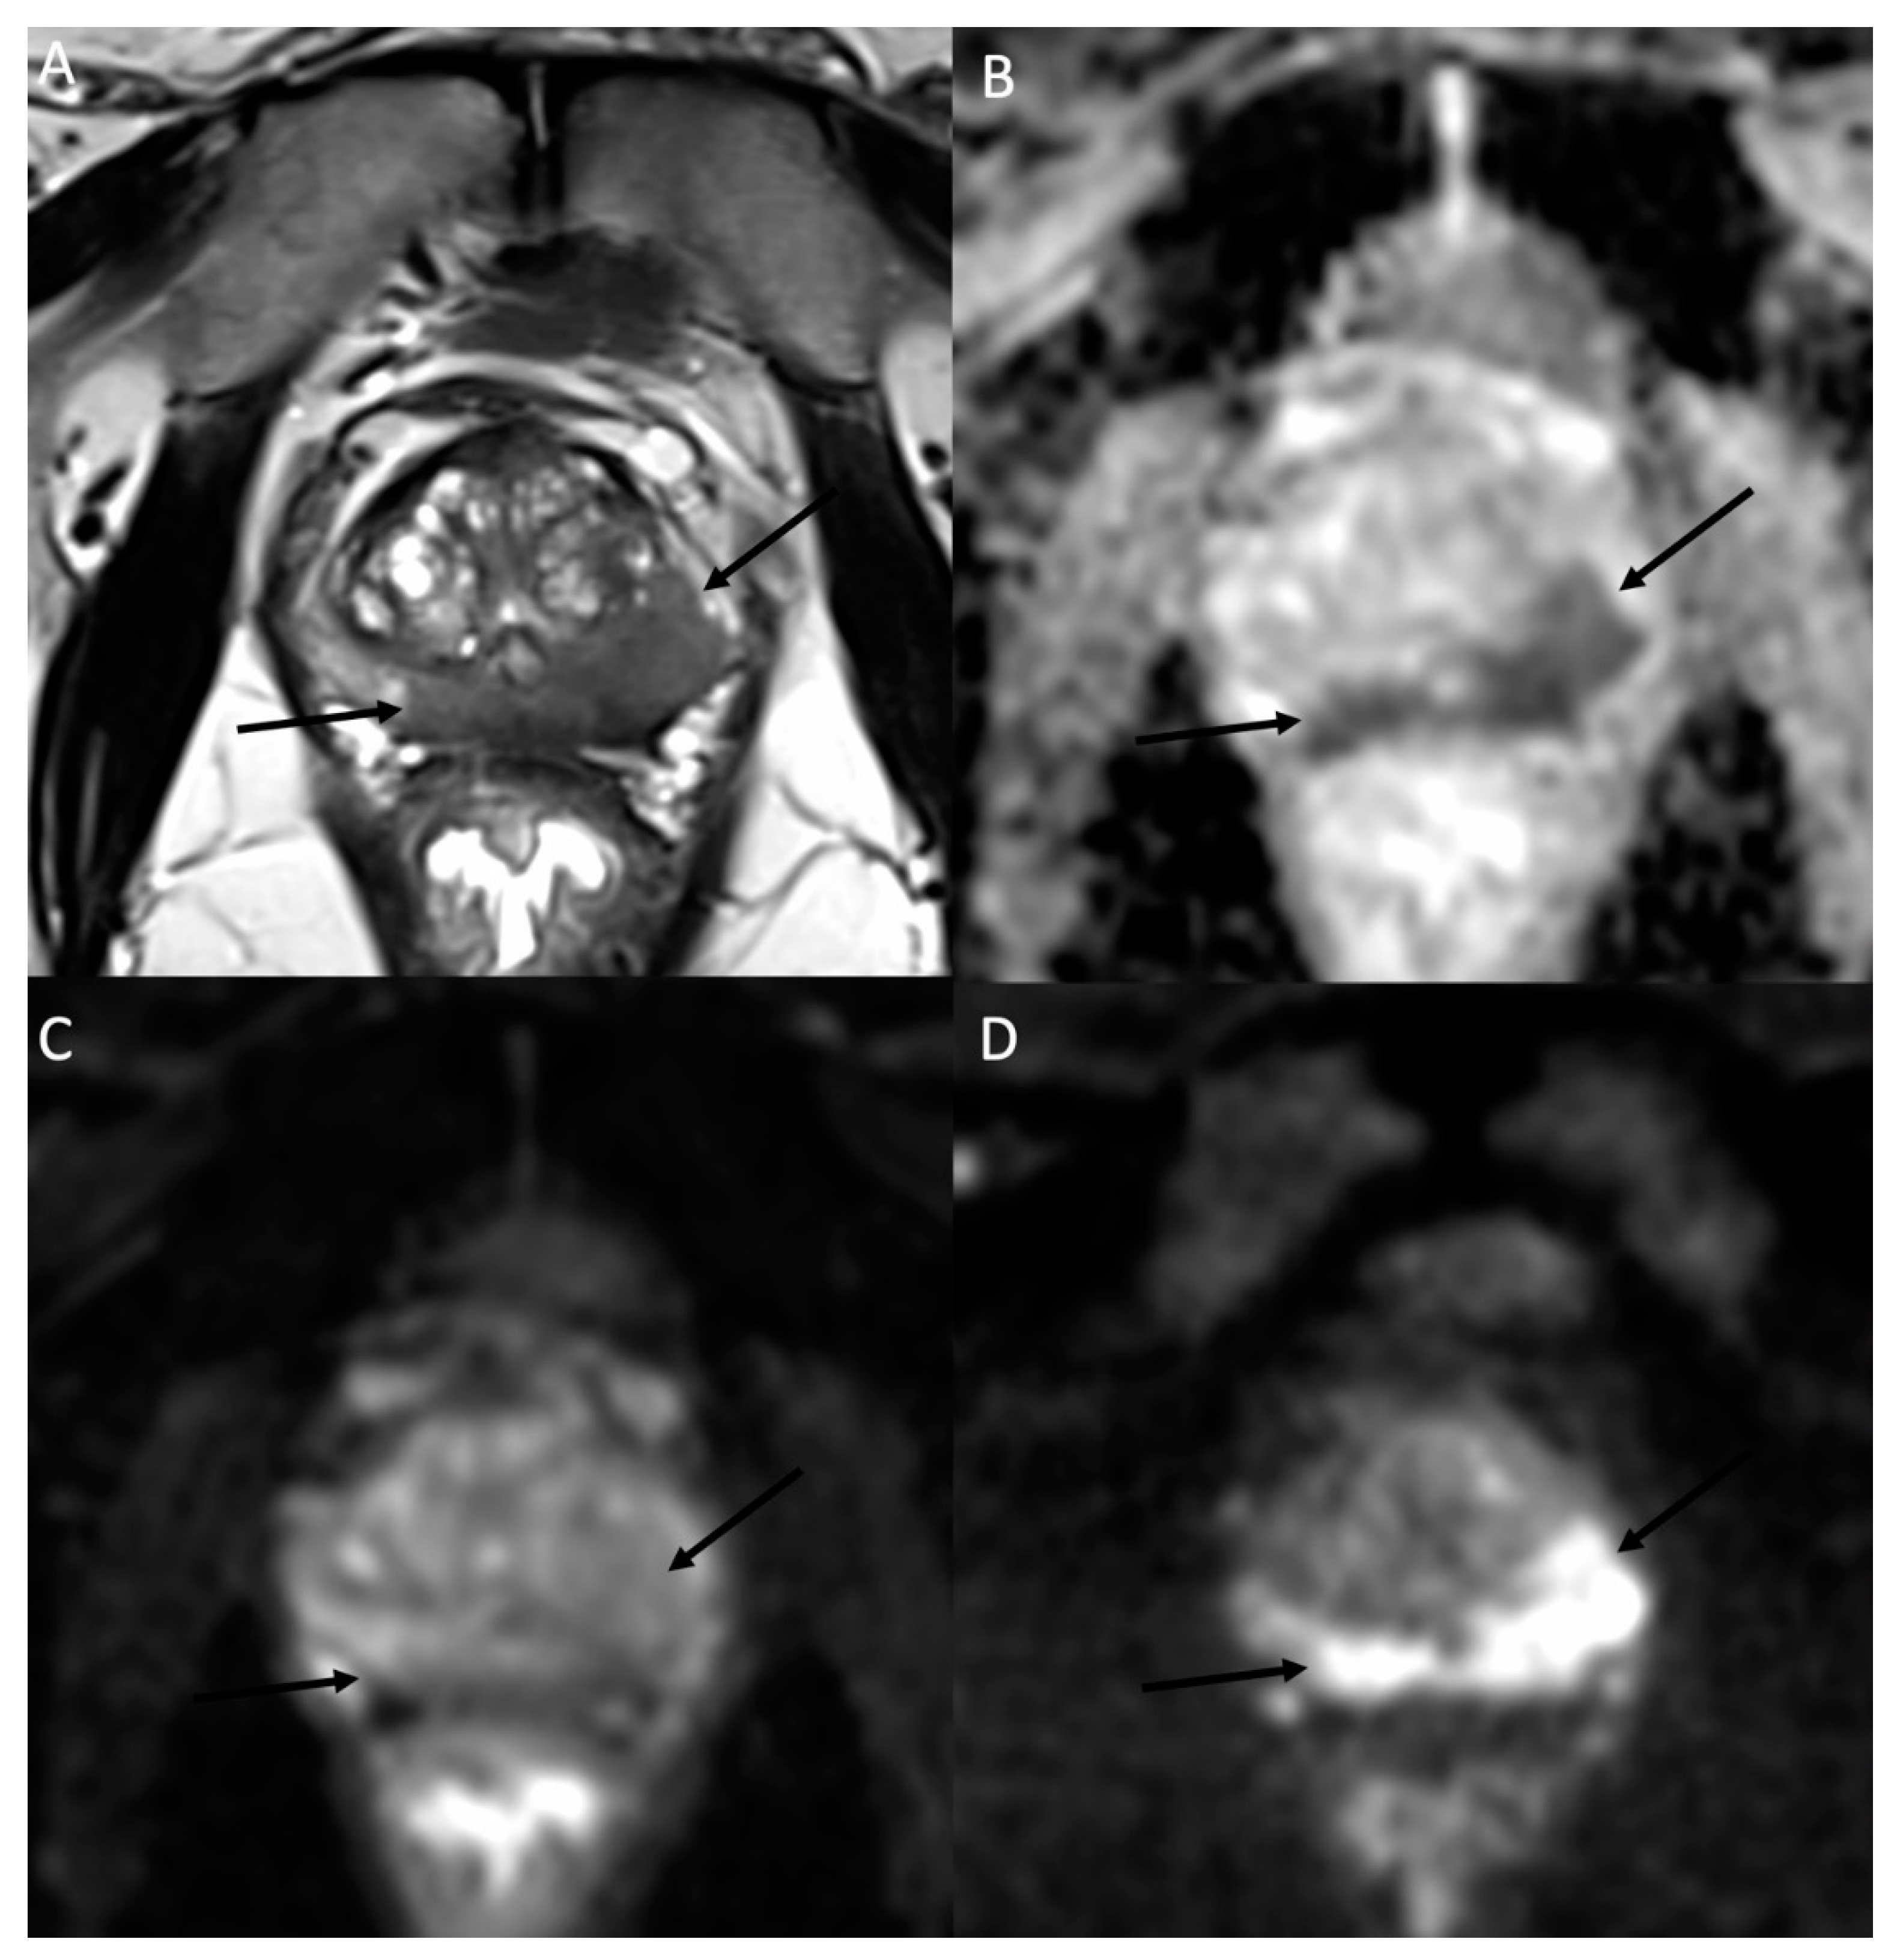

Figure 5.

Histologically proven left ovary adenocarcinoma in a 64-year-old woman. (A) T2W hyperintense heterogeneous left adnexal mass next to the uterus (*). Tissular bilobed left adnexal mass with parts of low (B) ADC values and high (C) b-1000 signal consistent with a diffusion restriction in the lesion (C). Post injection of gadolinium (D) T1W sequence with fat-saturation shows a heterogeneous enhancement (arrow).